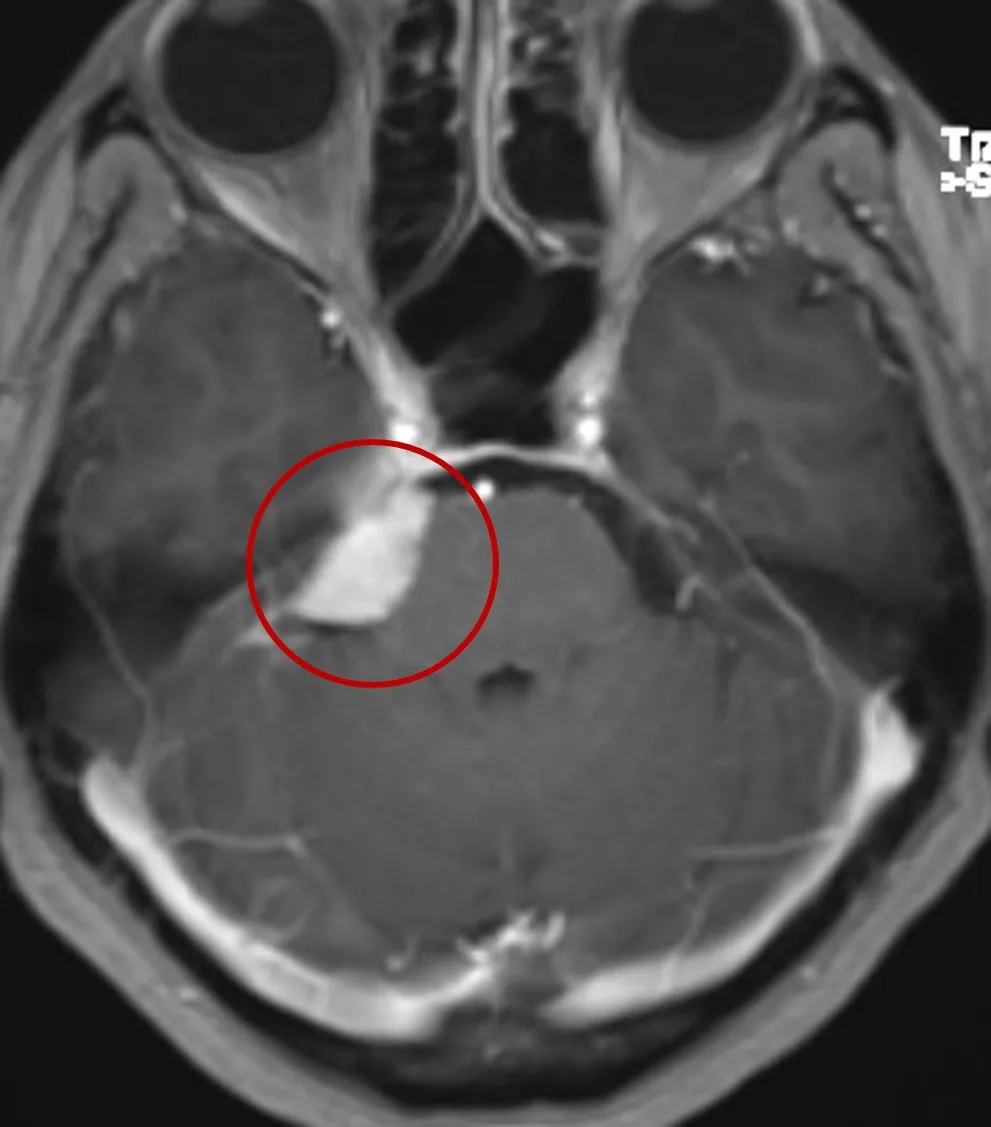

例如:我在CPA区生活

出生在大脑与小脑之间的硬脑膜隔上

属于颅底和脑深部肿瘤

与三叉神经、面听神经、外展神经、小脑、海绵窦等

诸多重要脑组织及功能神经都是亲密无间的好朋友

冲破CPA区,结识岩斜区的朋友们

从此我不再是小小的CPA区脑膜瘤

而是大岩斜区脑膜瘤

很多重要功能神经、脑组织、血管

见了我都要退避三舍呢

脑膜瘤沿着脑膜及自然间隙增大,继续侵犯M腔,从颅后窝跨越颅中窝并侵犯海绵窦,可进一步压迫损伤视神经、动眼神经、三叉神经等